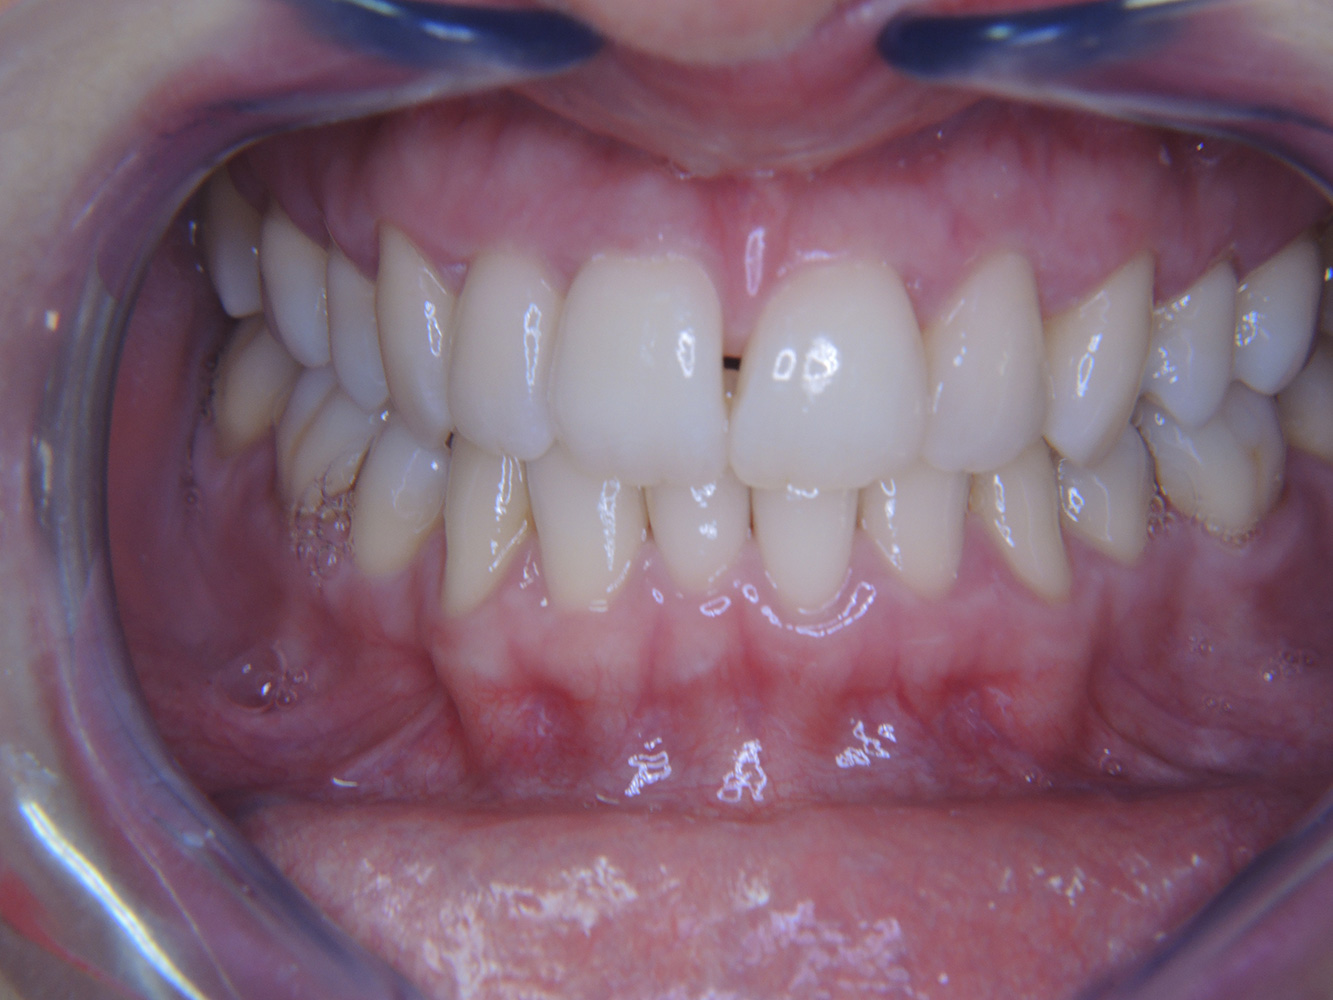

Fallpräsentation: Management komplexer Zahnprothetik

Es ist längst bekannt, dass Mundgesundheit und Allgemeingesundheit in direktem Zusammenhang stehen und einen zum Teil bidirektionalen Einfluss aufeinander haben. Die Berücksichtigung beider Faktoren sind bei der Planung der oralen Prävention und Therapie der Patienten in der Zahnarztpraxis unabdingbar. Dabei ist oberstes Ziel, die Gesundheit und die Lebensqualität der Patienten sowohl aus zahnmedizinischer -und medizinischer Sicht zu erhalten. mehr Infos